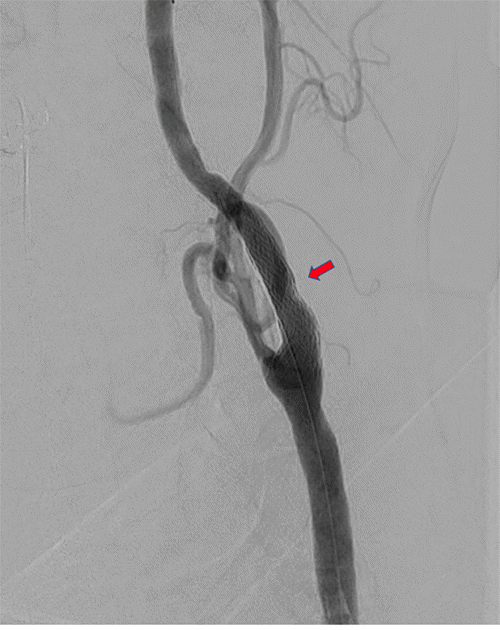

After expedited preoperative evaluation and medical optimization, the patient was taken to the hybrid suite for left TCAR under general anesthesia with cerebral oximetry. Carotid angiogram via direct proximal cervical common carotid artery exposure demonstrated severe focal ICA stenosis, corresponding with preoperative imaging (Figure 2A). After systemic anticoagulation and initiation of flow reversal via right femoral vein access, angioplasty of the left ICA was performed with a 5 × 20 mm balloon, followed by deployment of a 10 × 40 mm ENROUTE Transcarotid Stent (Silk Road Medical, Sunnyvale, CA) across the stenosis extending from the distal common carotid to the mid-ICA (in order to incorporate the ICA dissection). Completion angiogram demonstrated successful stent deployment with widely patent common, internal, and external carotid arteries (Figure 2B). The patient awoke without neurologic deficits. After surgery, he reported no headaches or further episodes of amaurosis fugax or other neurological events. Following one more day of blood pressure control management, he was discharged home with a prescription for clopidogrel. A plan was made for elective Right TCAR after a minimum of six weeks. The decision for a six-week interval was based on surgeon preference. While there is no conclusive data supporting simultaneous carotid interventions, many surgeons concur that waiting for recovery and monitoring hemodynamic and neurological function afterward may be safer, particularly for high-risk patients with severe stenotic lesions prone to reperfusion syndrome.

Figure 2. Left Carotid Angiogram During TCAR Procedure Before A) and After B) Angioplasty and Stent Deployment. Published with Permission

A.

B.